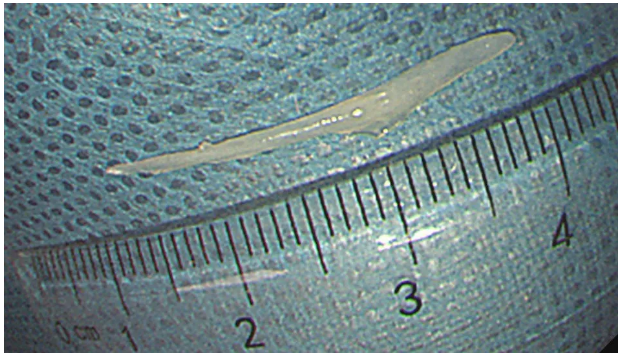

消化内镜室迅速启动取刺准备,当胃镜缓缓抵达食管入口时,清晰可见一根长约3cm的鱼刺,正斜斜嵌顿在食管入口的右侧壁,鱼刺尖端已刺入黏膜下层,周围黏膜因刺激出现明显充血水肿。更棘手的是,鱼刺恰好卡在食管入口的生理拐弯处,这个部位是食管与咽喉的衔接点,角度刁钻,内镜难以稳定固定位置。

紧接着,异物钳从内镜通道中缓缓伸出,借助豁口提供的充足空间,异物钳以最佳角度顺利接近鱼刺,精准地夹住了鱼刺。医生确认夹持牢固后,保持异物钳与胃镜轴线平行,缓慢退镜。退镜过程中,透明帽始终包裹着鱼刺,有效避免了鱼刺尖端划伤食管壁。当胃镜退出口腔时,那根让陈女士痛苦不已的鱼刺被完整取出。